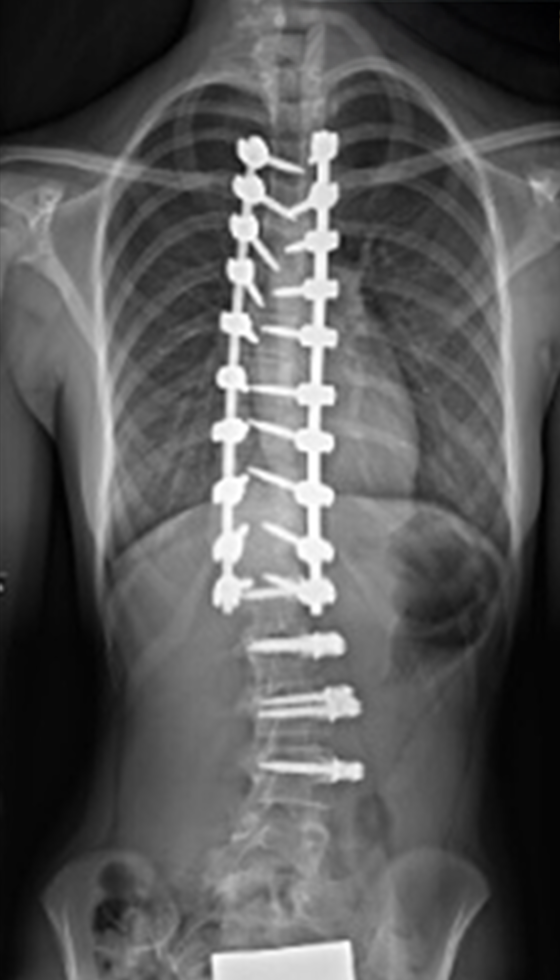

Gallery : Before - After